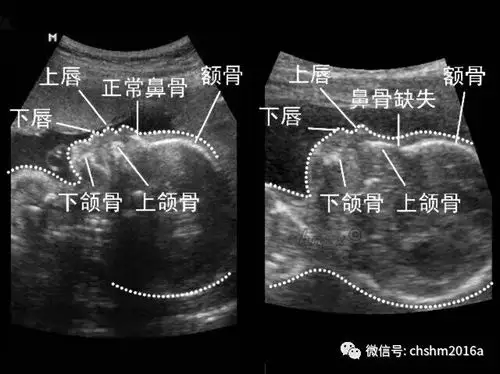

产科超声软指标